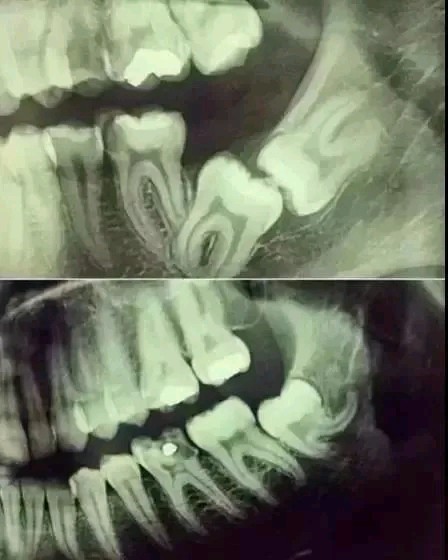

对于第一次来口腔医院检查或者已经出现严重口腔问题的患者,医生会建议先对口腔做一个X光或者CT扫描检查。毕竟肉眼只能看到牙齿露出的部分,对那些隐藏在牙龈、牙槽骨里面的情况医生无法精准判别。X光片可以透视出牙齿的内在情况,以便医生对牙齿情况有一个更全面的了解。